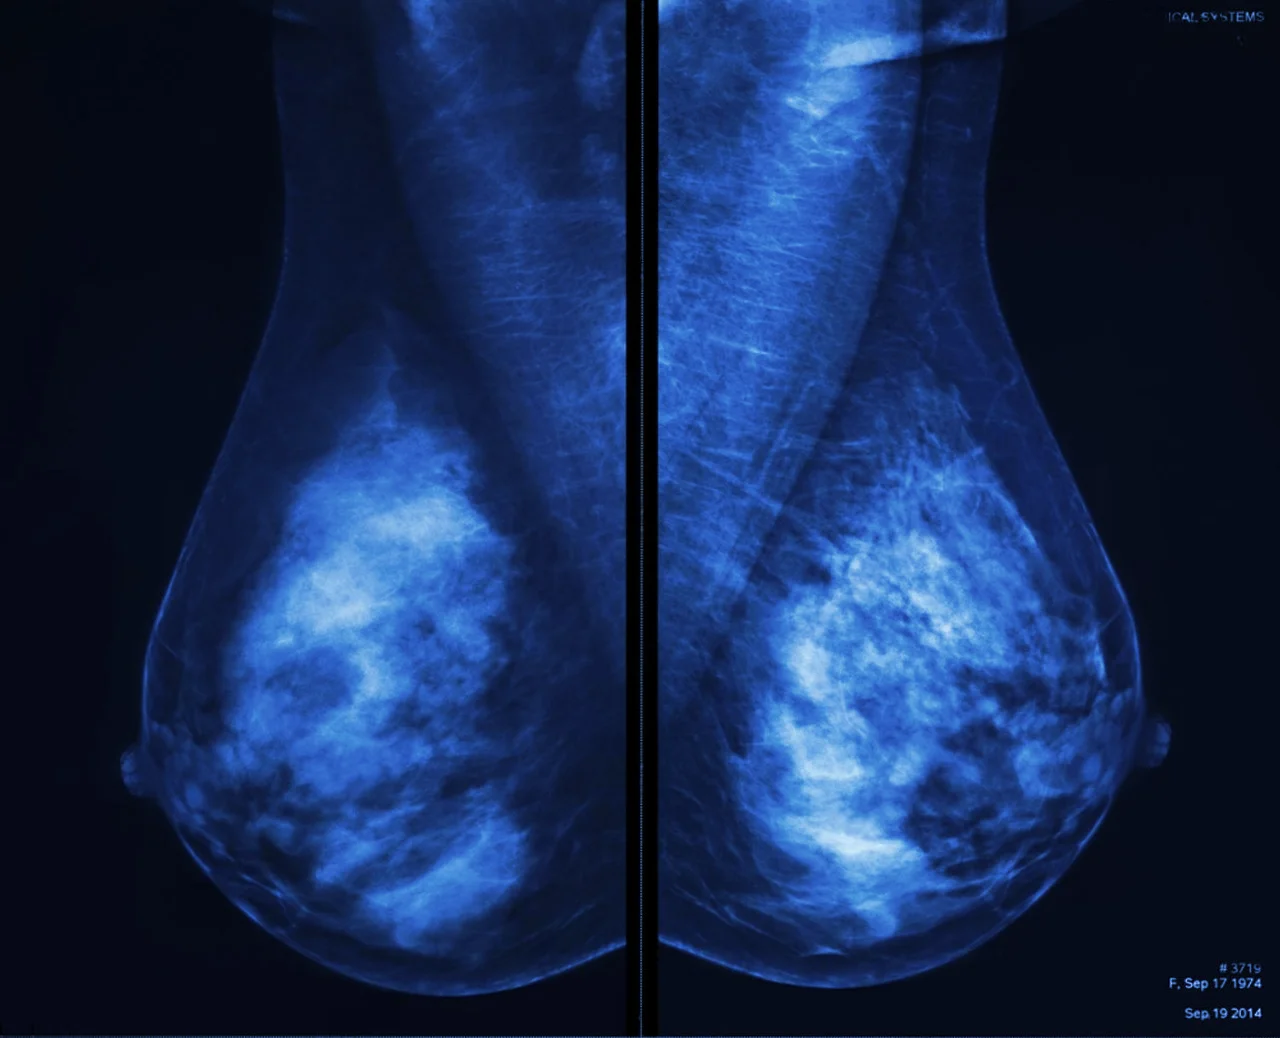

Estudios de imagen: mastografía y ultrasonido

La mastografía sigue siendo el estándar de oro para el tamizaje, permitiendo observar microcalcificaciones o nódulos que no son palpables. En mujeres jóvenes con tejido mamario denso, el ultrasonido complementa la evaluación. Estos estudios permiten definir como saber si tengo comienzo de cáncer mediante la observación de patrones de densidad y formas que el ojo clínico del radiólogo identifica como sospechosos.